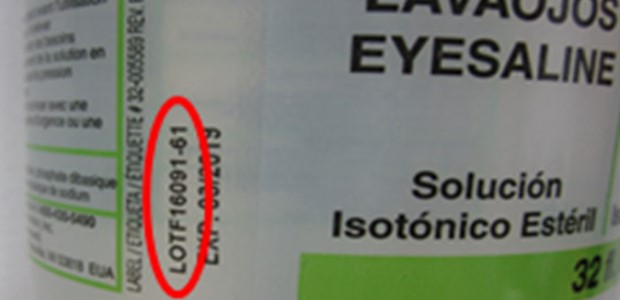

The company is making the recall in cooperation with FDA and indicated no injuries have been reported and it has not found any contamination in its batch testing, adding, "the voluntary recall is a precautionary measure due to a low risk of product contamination with Klebsiella pneumoniae.